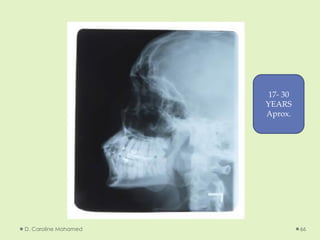

D. Caroline Mohamed 66

17- 30

YEARS

Aprox.

D. Caroline Mohamed66 17- 30 YEARS Aprox.